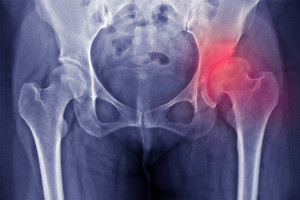

Dùng các loại glucocorticoid như prednisone có thể làm tăng nguy cơ mắc bệnh loãng xương. Dạng loãng xương này được gọi là loãng xương do glucocorticoid. Mặc dù điều chỉnh chế độ ăn uống và tập thể dục có thể giúp làm giảm nguy cơ loãng xương nhưng cũng có thể cần giảm liều glucocorticoid hoặc đổi thuốc khác.